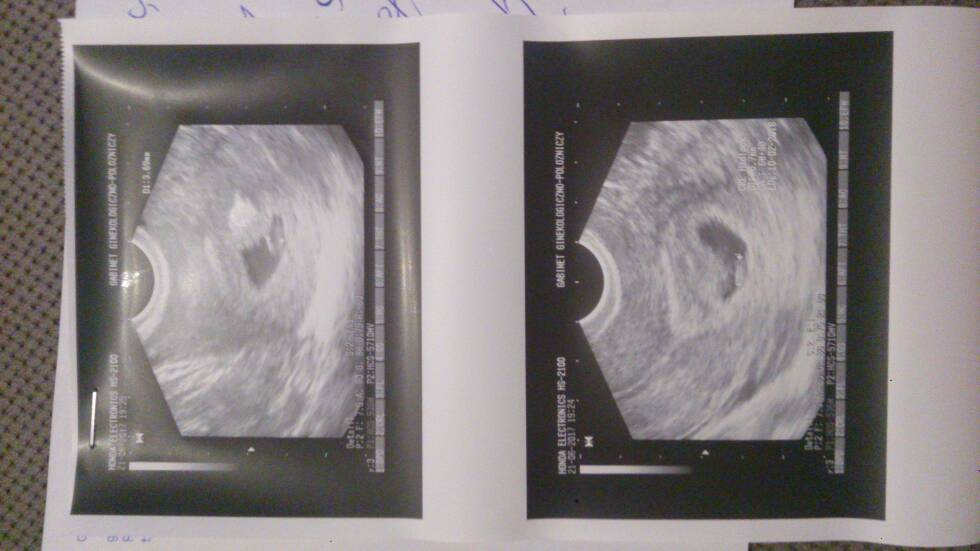

Widzialam serduszko:) pulsowalo:) lekarz powiedział ze wszystko ok..ze teraz na wizyte 12.07:) zalozyl karte ciazy :) Pozdrawiam

Ja podobnie jak u Ciebie mam inne terminy wg OM 8t0d a wg Usg 6t4d.Napewno miałyśmy opoznioną owulacje,stad te rozbieżności.

Dzisiaj byłam na wizycie, tak sie stresowalam ze zabralam męża ze sobą.....nareszcie zobaczyliśmy naszą fasolkę,ma 6,5mmserduszka jeszcze dokladnie nie bylo widać ale pulsowanie juz jest. Wszystko jest w porządku, mam zrobic wszystkie badania i za tydzien z wynikami bo kończy mi sie zwolnienie.

Termin na ok 13.02